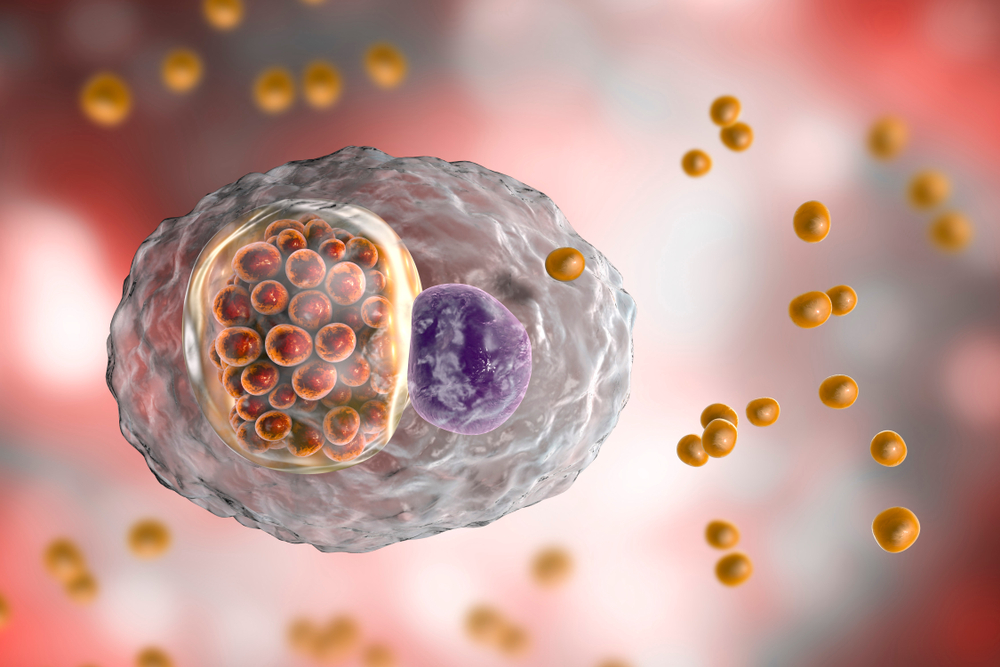

Фотографии бактерий, вызывающих бактериальные пневмонии у животных